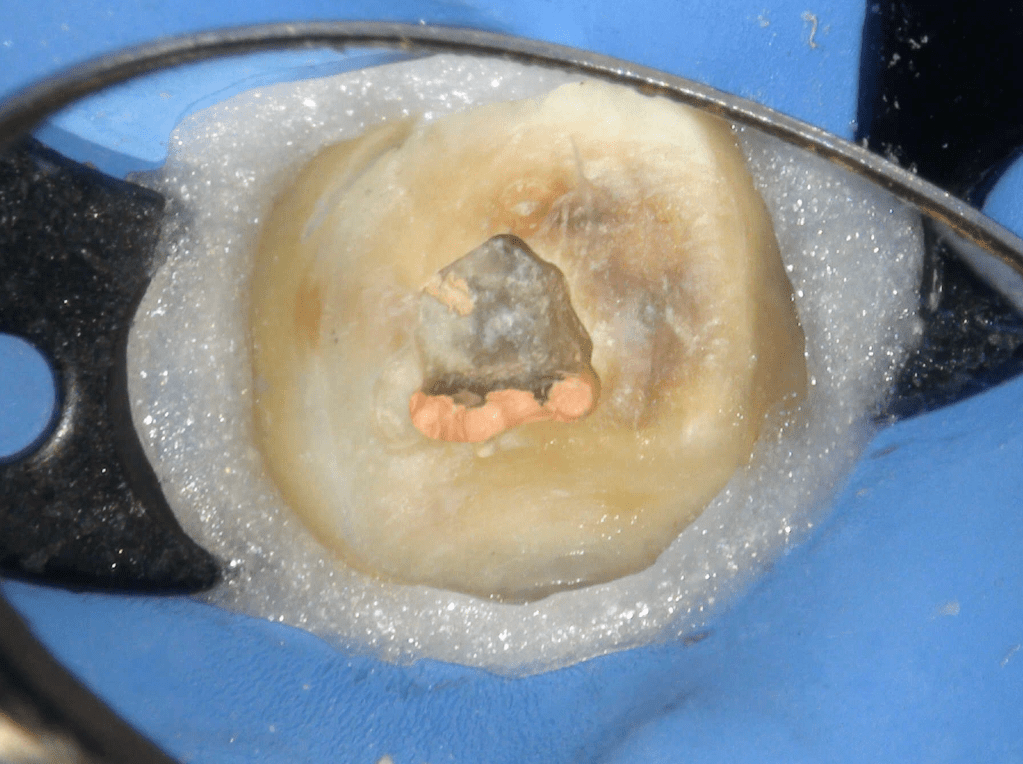

Molar superior

Reco preendo + 4 conductos molar superior